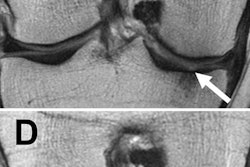

MR images of the right knee show signal abnormalities at baseline and subsequent defects at the 48-month follow-up. Above image shows a hyperintense signal abnormality in the patella at baseline (arrow). Image below shows the development of a fissure in the same patient (arrow) at 48 months. Images courtesy of Radiology.In an analysis by compartment, data revealed that cartilage signal abnormalities were most frequent in the patella (44 cases, 35%), followed by the lateral tibia (33 cases, 26%), trochlea (31 cases, 25%), medial femur condyle (10 cases, 8%), lateral femur condyle (7 cases, 6%), and medial tibia (1 case, 1%).